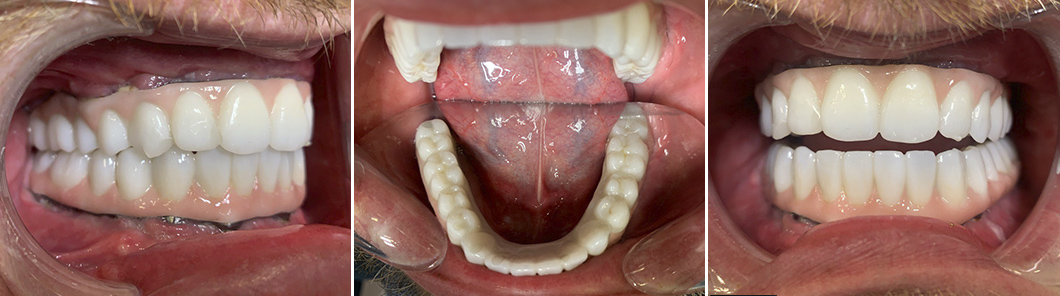

Были изготовлены 2 встречных протеза, опирающиеся на фрезерованные титановые балки. Материал коронок – диоксид циркония: 14 зубов в протезе верхней челюсти и 14 зубов в протезе нижней челюсти. Итого – 28 зубов в 2 полных зубных рядах.

Таким образом мы получили восстановление жевательной функции. Протезы были зафиксированы на мульти-юнит абатменты.

Через год я провел осмотр пациента К. т сделал контрольная ортопантомограмма. На снимке видно, что костная ткань сохранена в полном объеме. Пациент очень доволен итогом лечения, у него нет никакого дискомфорта, улыбка выглядит красиво и естественно. У К. хорошая гигиена, он следит за состоянием полости рта, поэтому моя рекомендация – раз в год посещать профилактический осмотр, делать ортопантомограмму и проводить профессиональную гигиену (тоже раз в год).